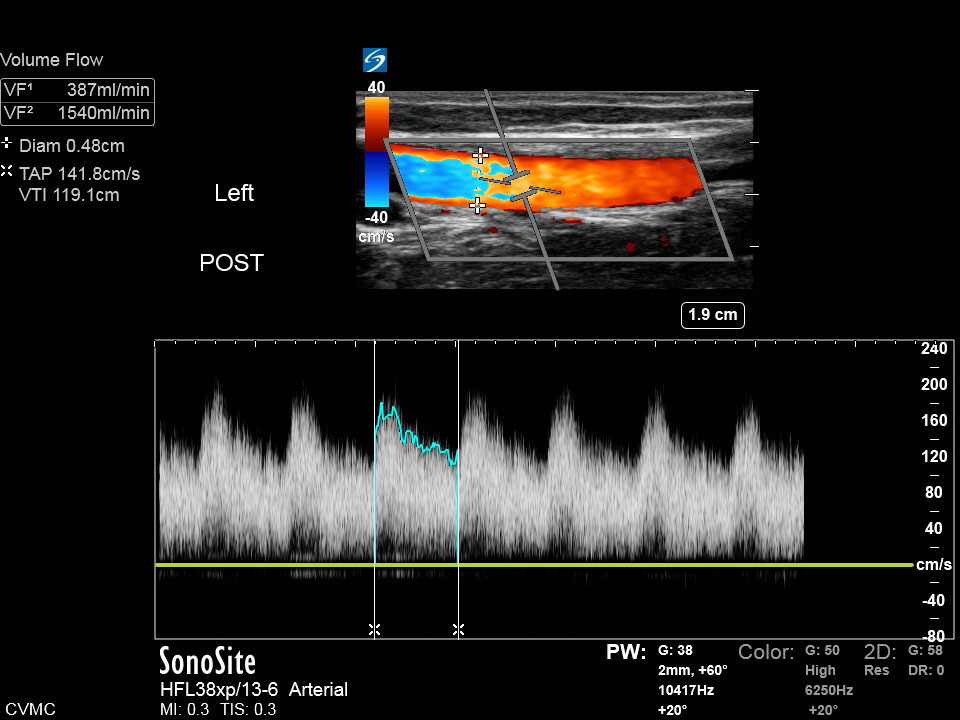

Dialysis Post AV Graft Color Volume Flow Image